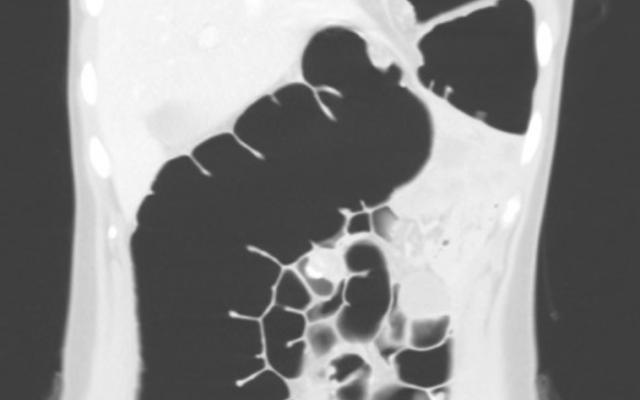

Een 28-jarige toeriste kwam bij de huisarts met hevige buikpijn en misselijkheid. Zij was die dag aangekomen op haar vakantiebestemming Curaçao. Ondanks de alarmerende klachtenpresentatie wilde zij niet doorgestuurd worden omdat haar zorgverzekering onvolledige dekking van de kosten gaf. Omdat de klachten toenamen, kwam zij de volgende dag naar de Spoedeisende Hulp. Uit de anamnese bleek dat drie maanden eerder bij haar een ongecompliceerde Nissen-fundoplicatie was verricht vanwege symptomatische gastro-oesofageale reflux bij haar eerdere obesitas. Bij een Nissen-fundoplicatie wordt het bovenste deel van de maag (de fundus) om de onderste slokdarmsfincter gewikkeld, om zo de terugstroom van maagzuur te…